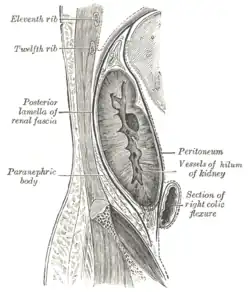

Sagittal section through posterior abdominal wall, showing the relations of the capsule of the kidney

Sagittal section through posterior abdominal wall, showing the relations of the capsule of the kidney -